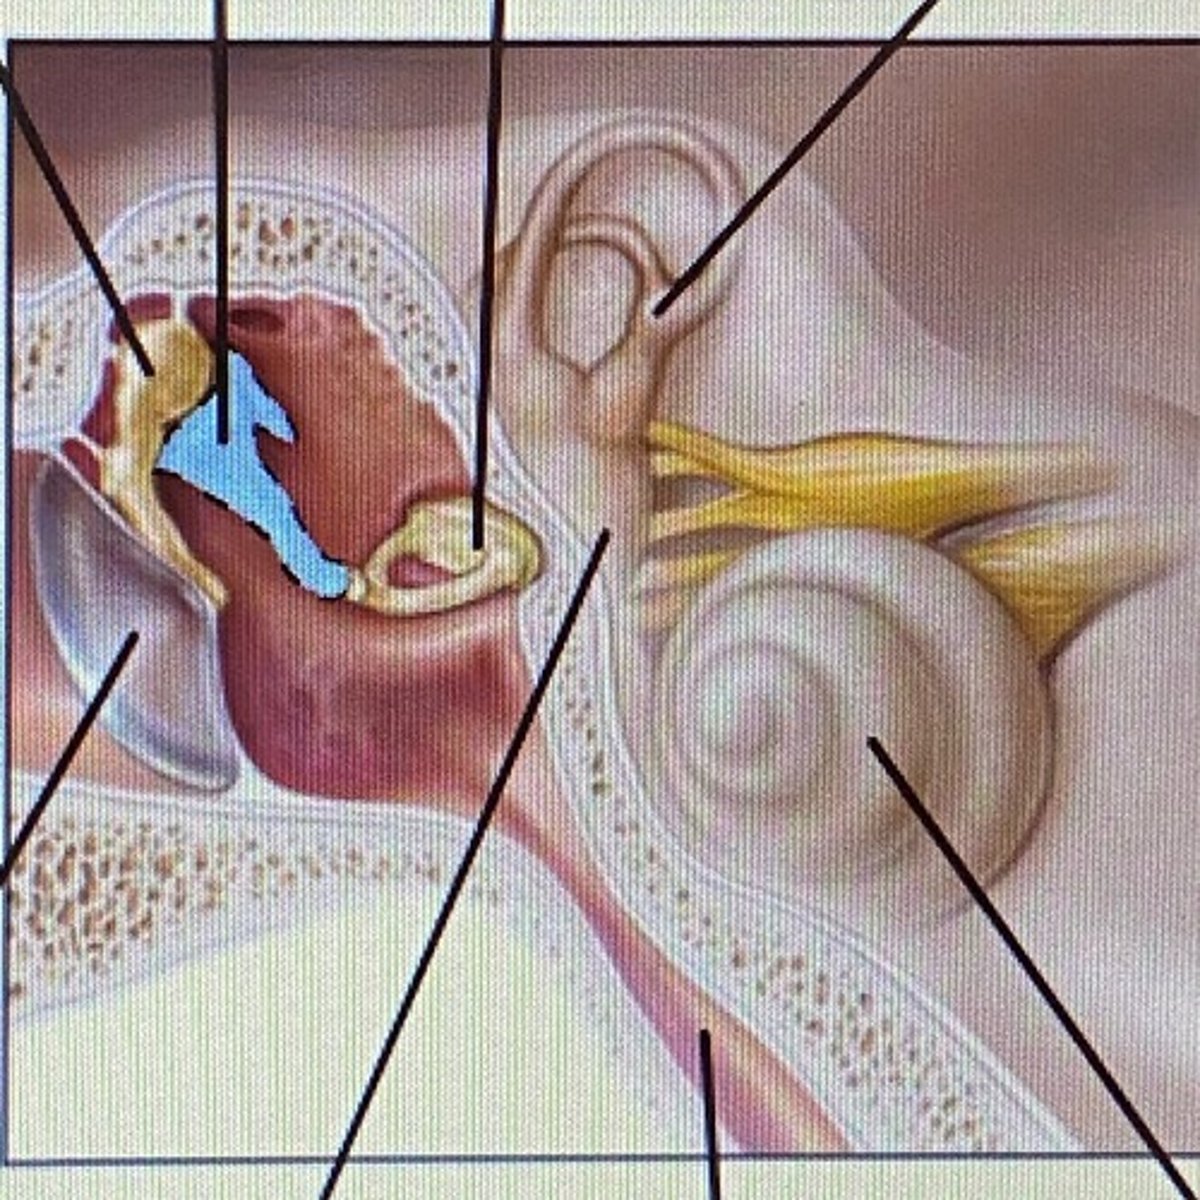

auricle

External Acoustic Meatus

vestibule

-functions in balance and equilibrium

Vestibulocochlear Nerve

- cranial nerve 8

Stapes

Incus

Malleus

Tympanic Membrane

pharyngotympanic tube

external ear

middle ear